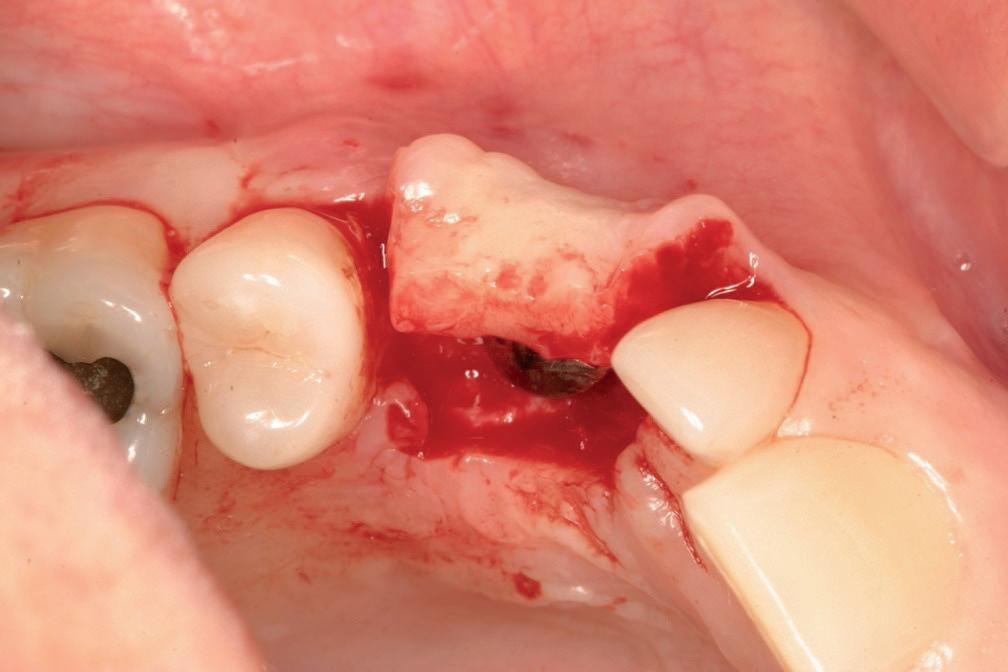

In het tweede kwadrant ziet de situatie er in eerste instantie röntgenologisch veel beter uit. Een vierdelige brug rust op twee pijlers: de 24—27. Ook hier is sprake van vermoedelijk agenesie van de 22. Bij nader onderzoek blijkt diepe cariës onder de kroon

de kaak. Voor een accuratere diagnostiek is een CBCT-scan nodig.

Dat de brug in het vierde kwadrant nog niet is losgekomen op de pijlers, is een wonder. De zesdelige brug is vervaardigd op vier pijlers: 43, 44, 45 en de 48. Zowel op de meegestuurde solo als op de OPT is secondaire cariës zichtbaar onder de kroon van de 44. Bij de 45 is een poging gedaan om secondaire cariës cervicaal te behandelen met composiet. Parodontaal is de 45 mogelijk het slechtst eraan toe. De 45 vertoont zeer verdiepte en ontstoken pockets tot 9 mm met gingivarecessie tot 2-4 mm. Er is dus sprake van aanhechtingsverlies tot 11 mm en röntgenologisch lijkt er sprake te zijn van een angulair defect bij zowel de 44 als de 45. Beide elementen zijn endodontisch behandeld. De prognose van beide elementen is dus slecht.